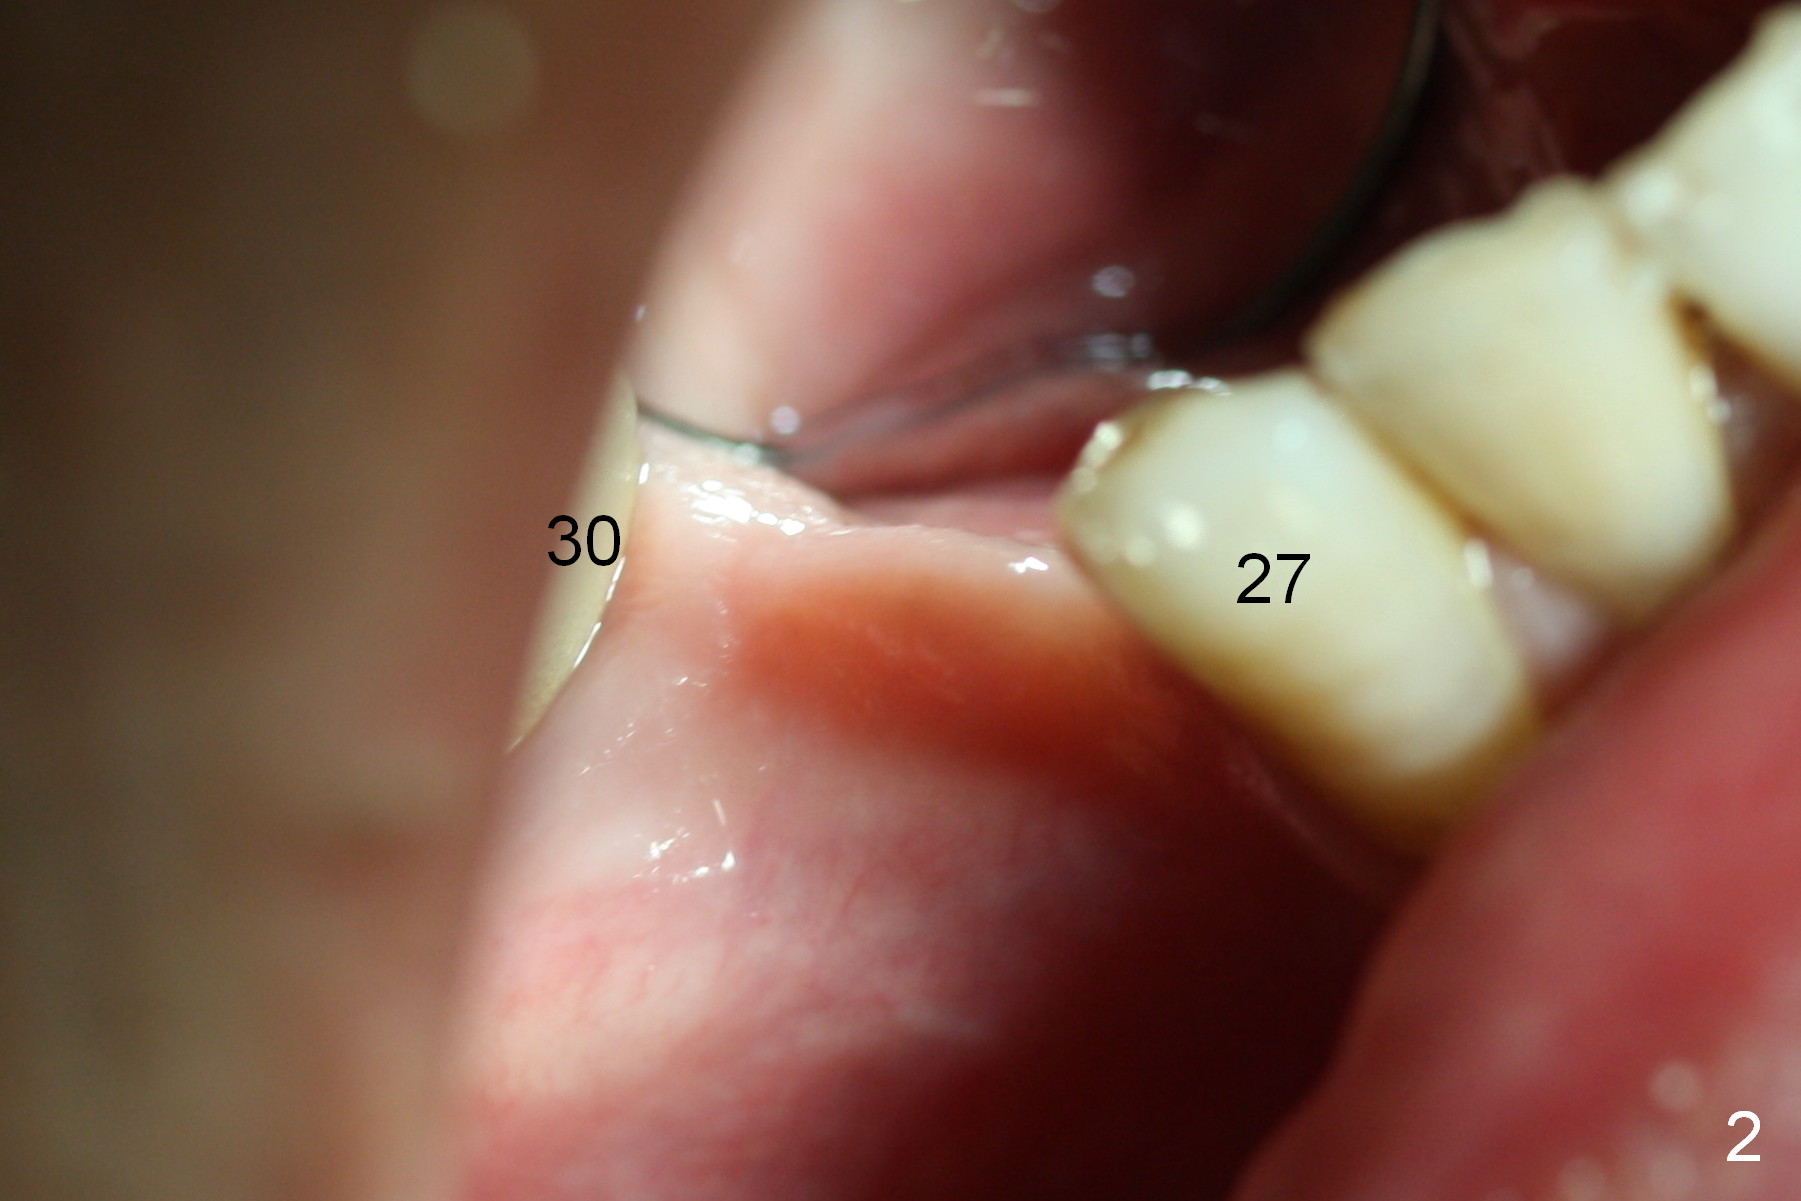

The 1st intraop PA taken after initial osteotomy at the depth of 12 mm shows that the mental loop (Fig.4 red dashed line) appears to be more superior than what is expected from CBCT study; while the apical end of the osteotomy at #28 is going to be moved mesially (>), that at #29 distally (<). Both implants (3x14 and 4.5x12 mm) are placed with insertion torque 56 Ncm (Fig.5). After placement of a 5.8x4(2) mm abutment at #29, an immediate provisional is fabricated and cemented (Fig.6 P). The partial is modified and the left portion is seated (Fig.6 <). The patient is pleased with the change: from removable to fixed appliance. There is no paresthesia postop.